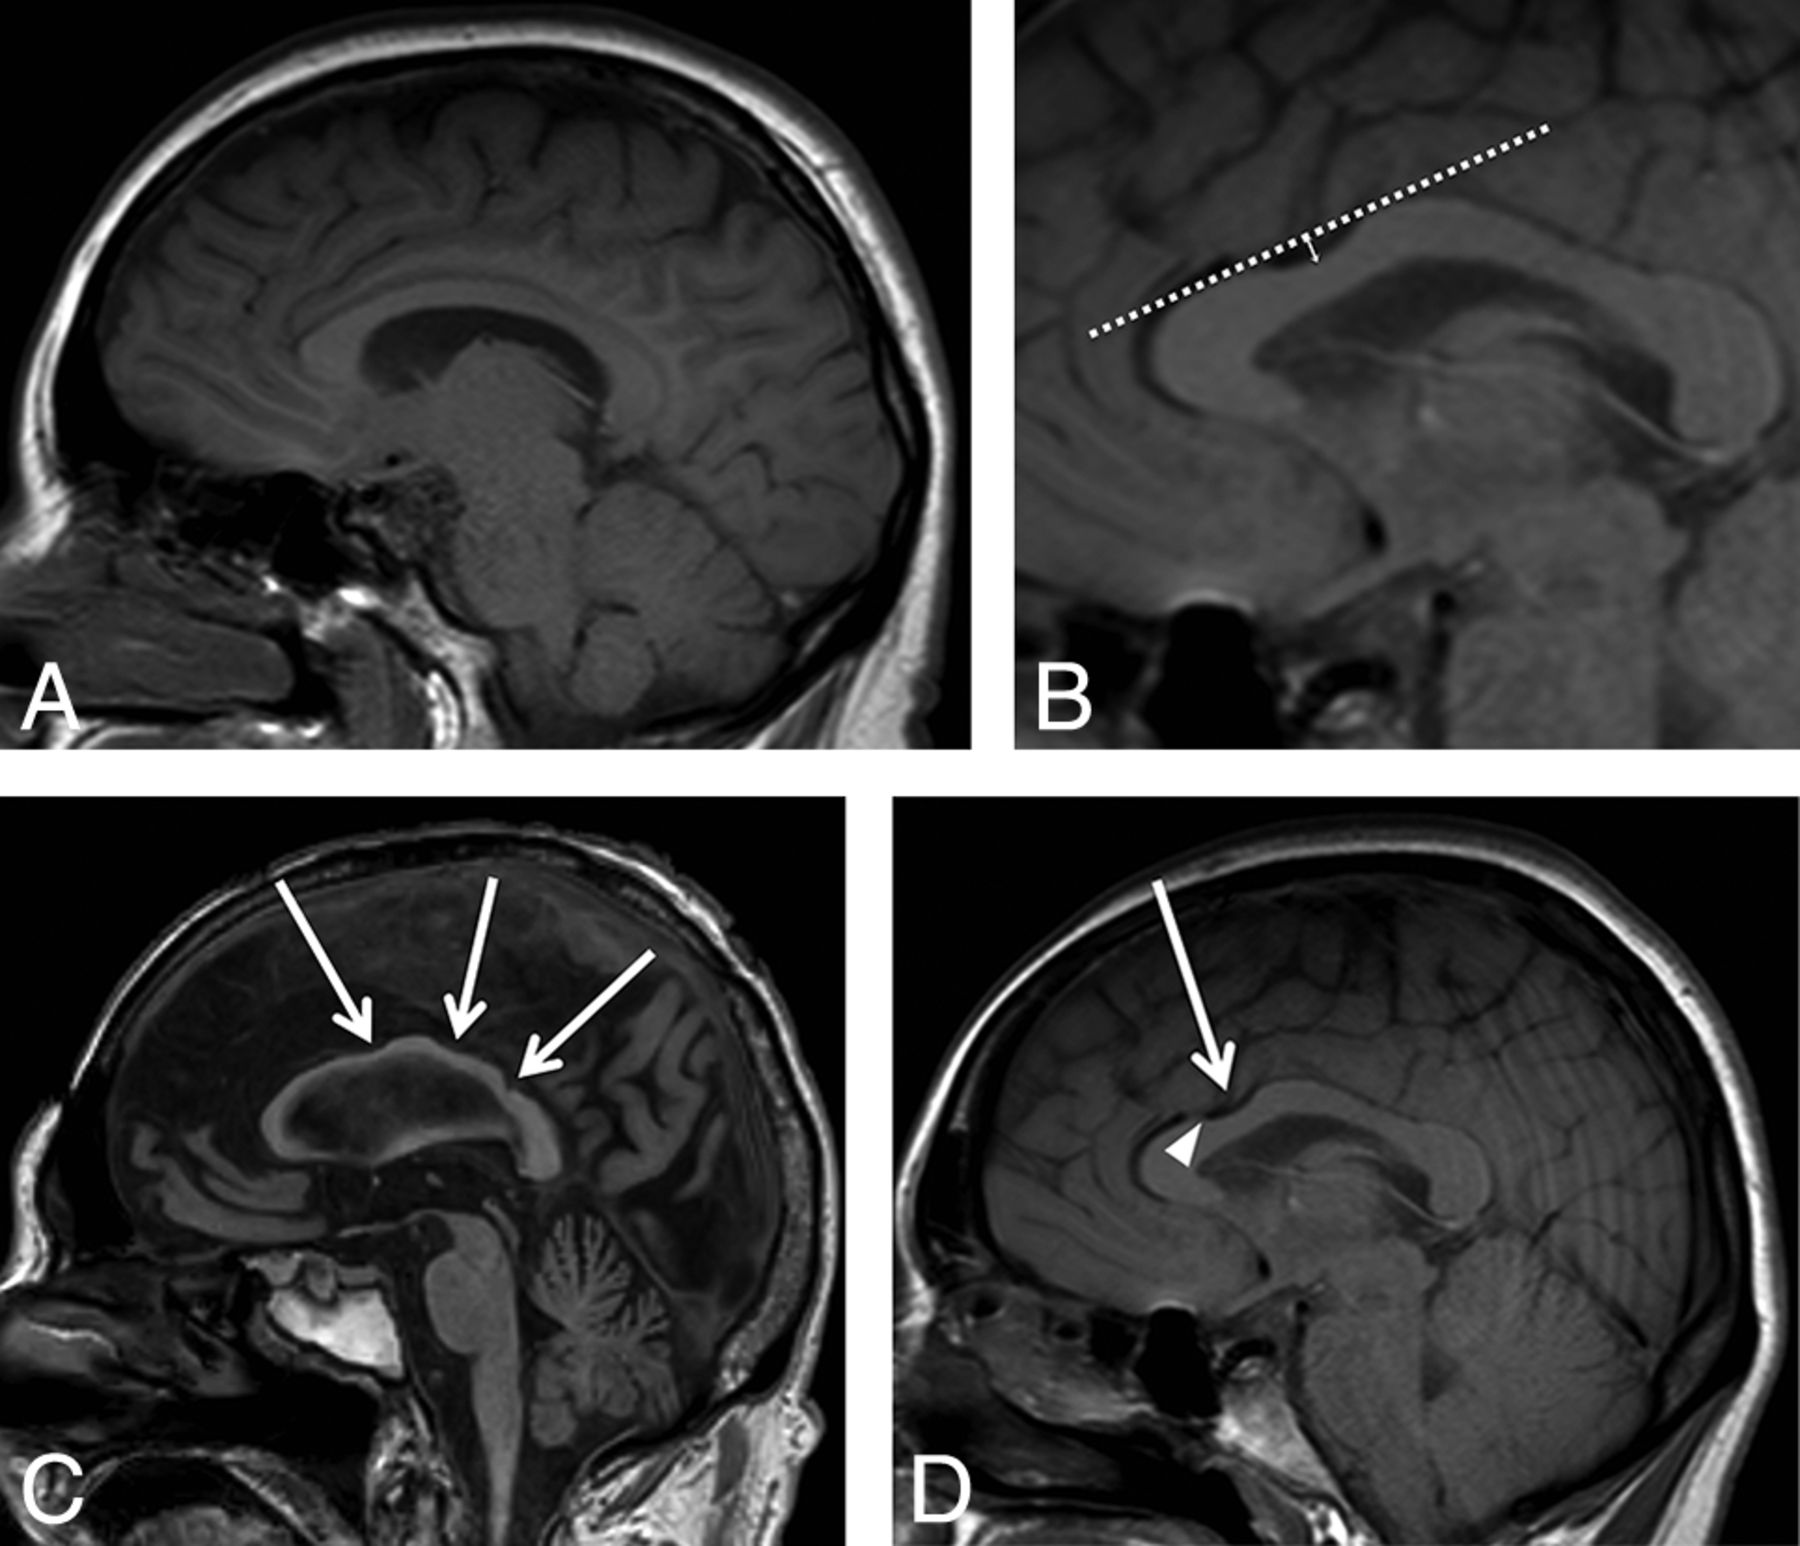

A team of neuroradiologists and neurosurgeons then visually inspected the dorsal surface of each CC on a midline sagittal T1-weighted image. A CC was designated “normal” if the dorsal surface contained no notching (Fig 1A). A “notch” was defined as a focal concavity in the dorsal surface the depth of which was at least 1 mm from a tangential line to the surface of the CC (Fig 1B). The notch was noted to be in either the anterior or posterior half of the body of the CC. The CC was considered “undulating” if there were >2 notches, including both an anterior and posterior notch (Fig 1C). The depth and location of the notch was recorded. Each image was also examined for the presence of a visible pericallosal artery flow void and whether the artery was seen within the notch (Fig 1D).

A, Midline sagittal T1-weighted image shows an example of a normal corpus callosum without evidence of anterior or posterior notching. B, A “notch” was defined as a depression in the dorsal surface whose depth was at least 1 mm from a tangential (dashed) line to the surface of the CC. The solid arrow line shows a 3-mm-deep anterior notch. C, Three areas of notching indicated by the white arrows correspond to an undulating configuration. D, Midline sagittal T1-weighted image shows that a 3-mm anterior notch (arrow) is present. The flow void from the pericallosal artery is visualized extending into the notch (arrowhead).